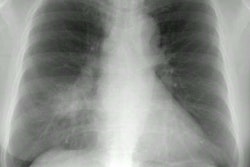

CXR demonstrates migratory infiltrates, but after 1 to 2 months the lesions become stable nodules or cysts predominantly in the lower lobes. Pleural effusions can be seen.CT findings include poorly marginated peripheral or subpleural nodules measuring approximately 2cm (up to 74% of cases) with surrounding ground-glass and a streaky opacity connecting the nodule to the pleural surface [3], pleural effusion, hydropneumothorax, airspace consolidation, and thin walled cysts [1,2].